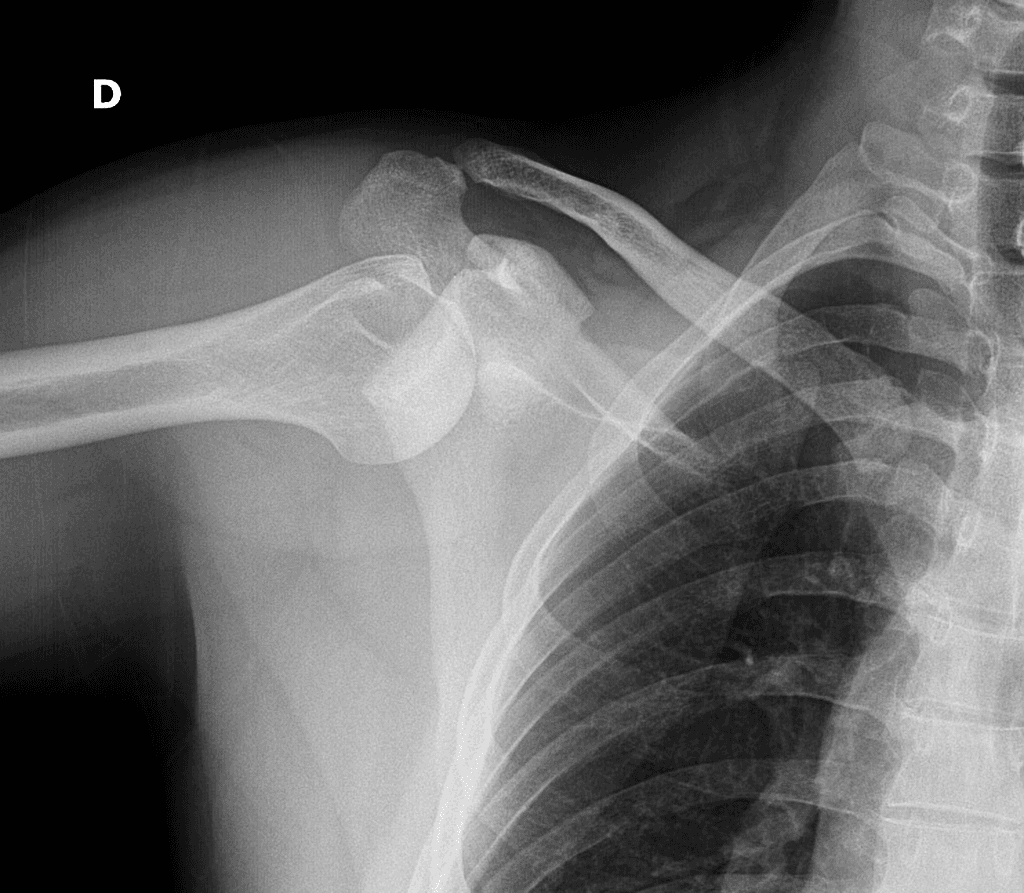

Ca bệnhTrật khớp vai tái phát

Trật khớp vai tái phát

Tiền sử trật khớp tái hồi

Trật khớp vai tái hồi

- 1.Tổn thương Bankart

- 2.Tổn thương Hill-Sachs

Trật khớp tái hồi thường gặp ở khớp vai, thường là kết quả của một chấn thương ban đầu làm tổn thương các cấu trúc ổn định như sụn viền ổ chảo hoặc bao khớp, dẫn đến tình trạng mất vững mạn tính.